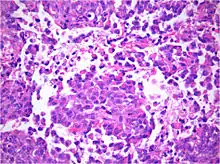

AT/RT and rhabdoid tumor share the term "rhabdoid" because under a microscope, both tumors resemble rhabdomyosarcoma.

Histology

The tumor histopathology is jumbled small and large cells. The tissue of this tumor contains many different types of cells including the rhabdoid cells, large spindled cells, epithelial and mesenchymal cells, and areas resembling primitive neuroectodermal tumor (PNET). As much as 70% of the tumor may be made up of PNET-like cells. Ultrastructure characteristic whorls of intermediate filaments are seen in the rhabdoid tumors (as with rhabdoid tumors in any area of the body). Ho and associates found sickle-shaped embracing cells, previously unreported, in all of 11 cases of AT/RT.[16]

Immunohistochemistry

Immunohistochemical staining is widely used in the diagnosis and treatment of cancer. Specific molecular markers are characteristic of particular cancer types. Immunohistochemistry is also widely used in basic research to understand the distribution and localization of biomarkers in different parts of a tissue. Proteins found in an ATeratoid/RT are:

- Vimentin-positive

- Cytokeratin-positive

- Neuron specific enolase-positive

- Epitelial membrane antigen-positive

- Glial fibrillary acidic protein- positive

- Synaptophysin

- Chromogranin

- Smooth muscle actin

- Desmin

- Carcinoembrionary antigen

- CD99 antigen;[17][18]

- S-100

- neurofilaments

- AFP – not found

- HCG – negative